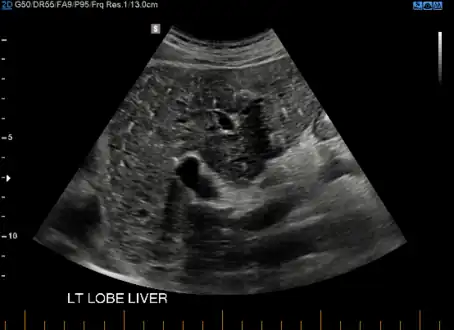

von Meyenburg Complex in ultrasound. Numerous little cysts with ringdown artefacts.